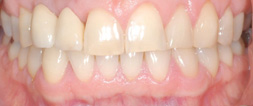

Since 1992, titanium screw implants have been inserted in edentulous sections of the upper and lower jaw in the clinic. Such dental implants serve as artificial tooth roots which, in combination with a tooth-crown-like superstructure (superstructure), enable the restoration of isolated tooth gaps with a crown, in the case of several missing teeth with a crown block, and finally in the case of an edentulous jaw with a fixed prosthesis.